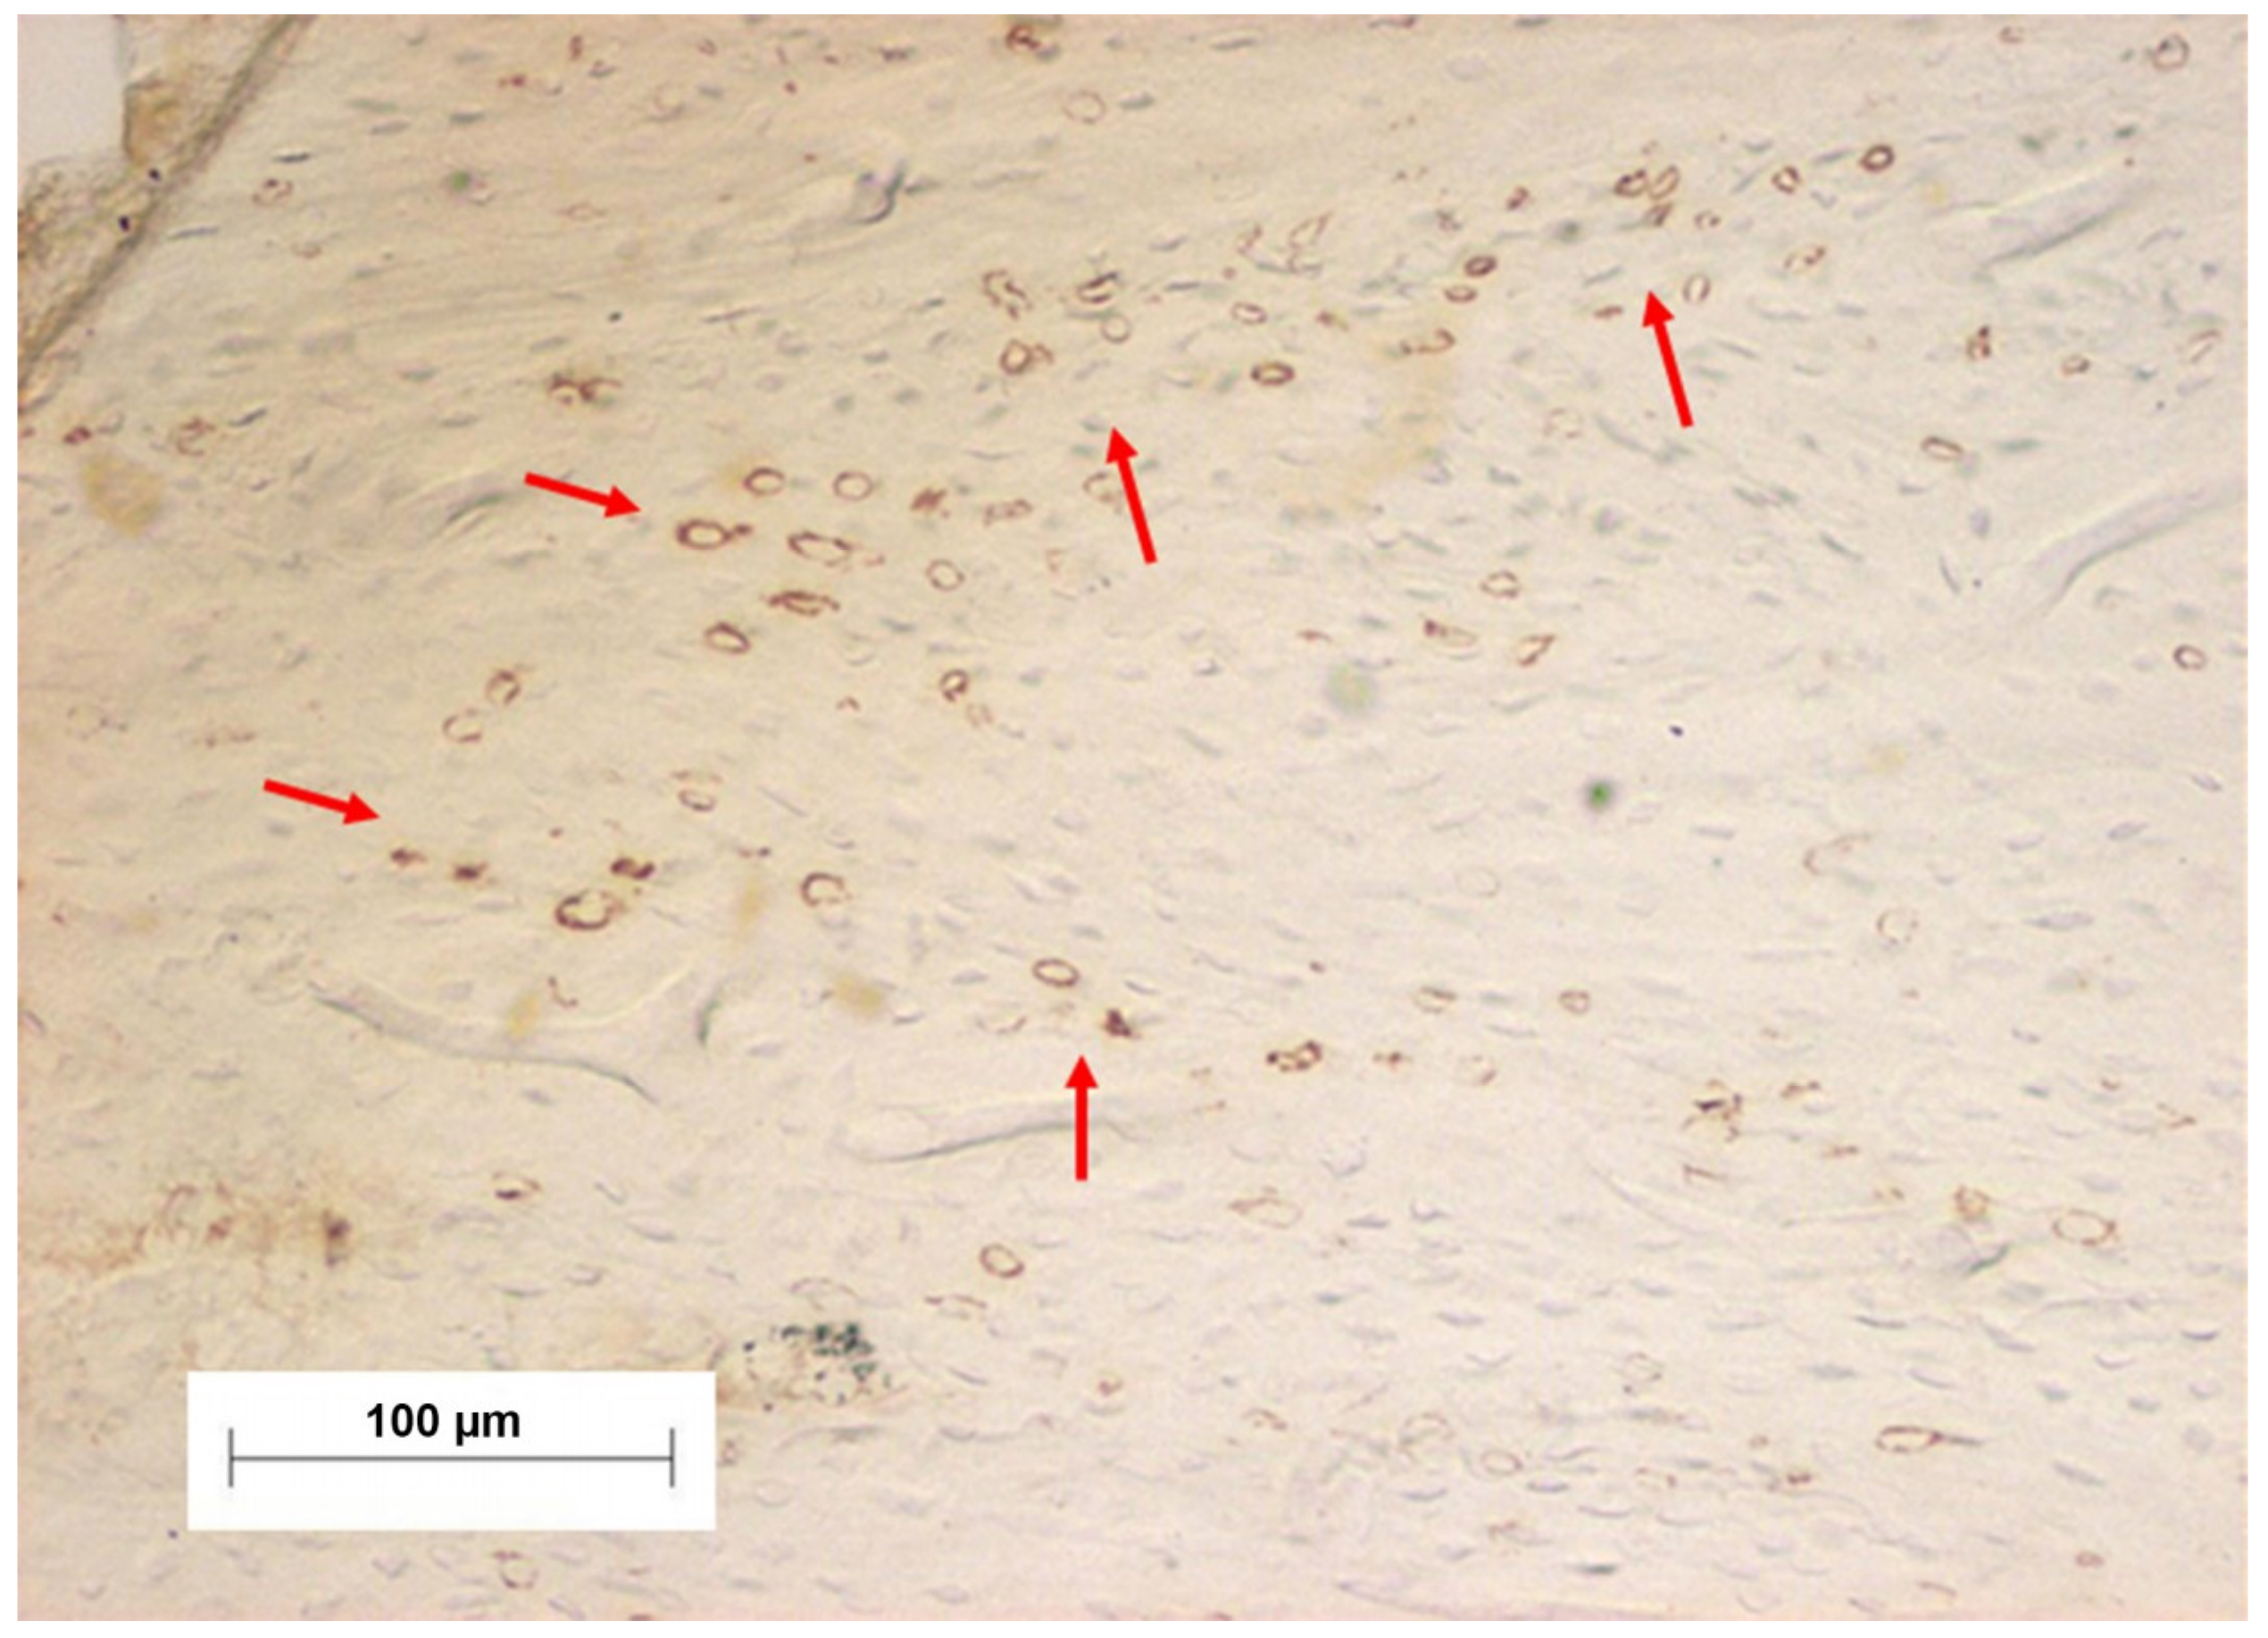

2.5. Immunohistochemical Process

- Salles, M.B.; Konig, B., Jr.; Allegrini, S., Jr.; Yoshimoto, M.; Martins, M.T.; Coelho, P.G. Identification of the nuclear factor kappa-beta (NF-κB) in cortical of mice Wistar using Technovit 7200 VCR(R). Med. Oral Patol. Oral Cir. Bucal 2011, 16, e124–e131. [Google Scholar] [CrossRef]